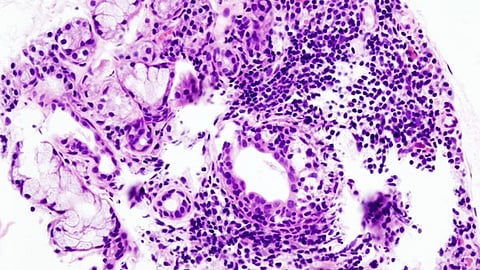

Sjogren’s is a chronic autoimmune connective tissue disorder affecting four million Americans plus an unknown number who are undiagnosed. Patients with this condition may also have other autoimmune disorders.

Sjogren's is difficult to diagnose because it has many symptoms which are similar to those of other conditions and there is no single, definitive test for Sjogren's. The most common symptoms include dryness of the mouth and eyes, tooth decay, fatigue and chronic pain. But major organ involvement, neuropathies and lymphomas may also occur.